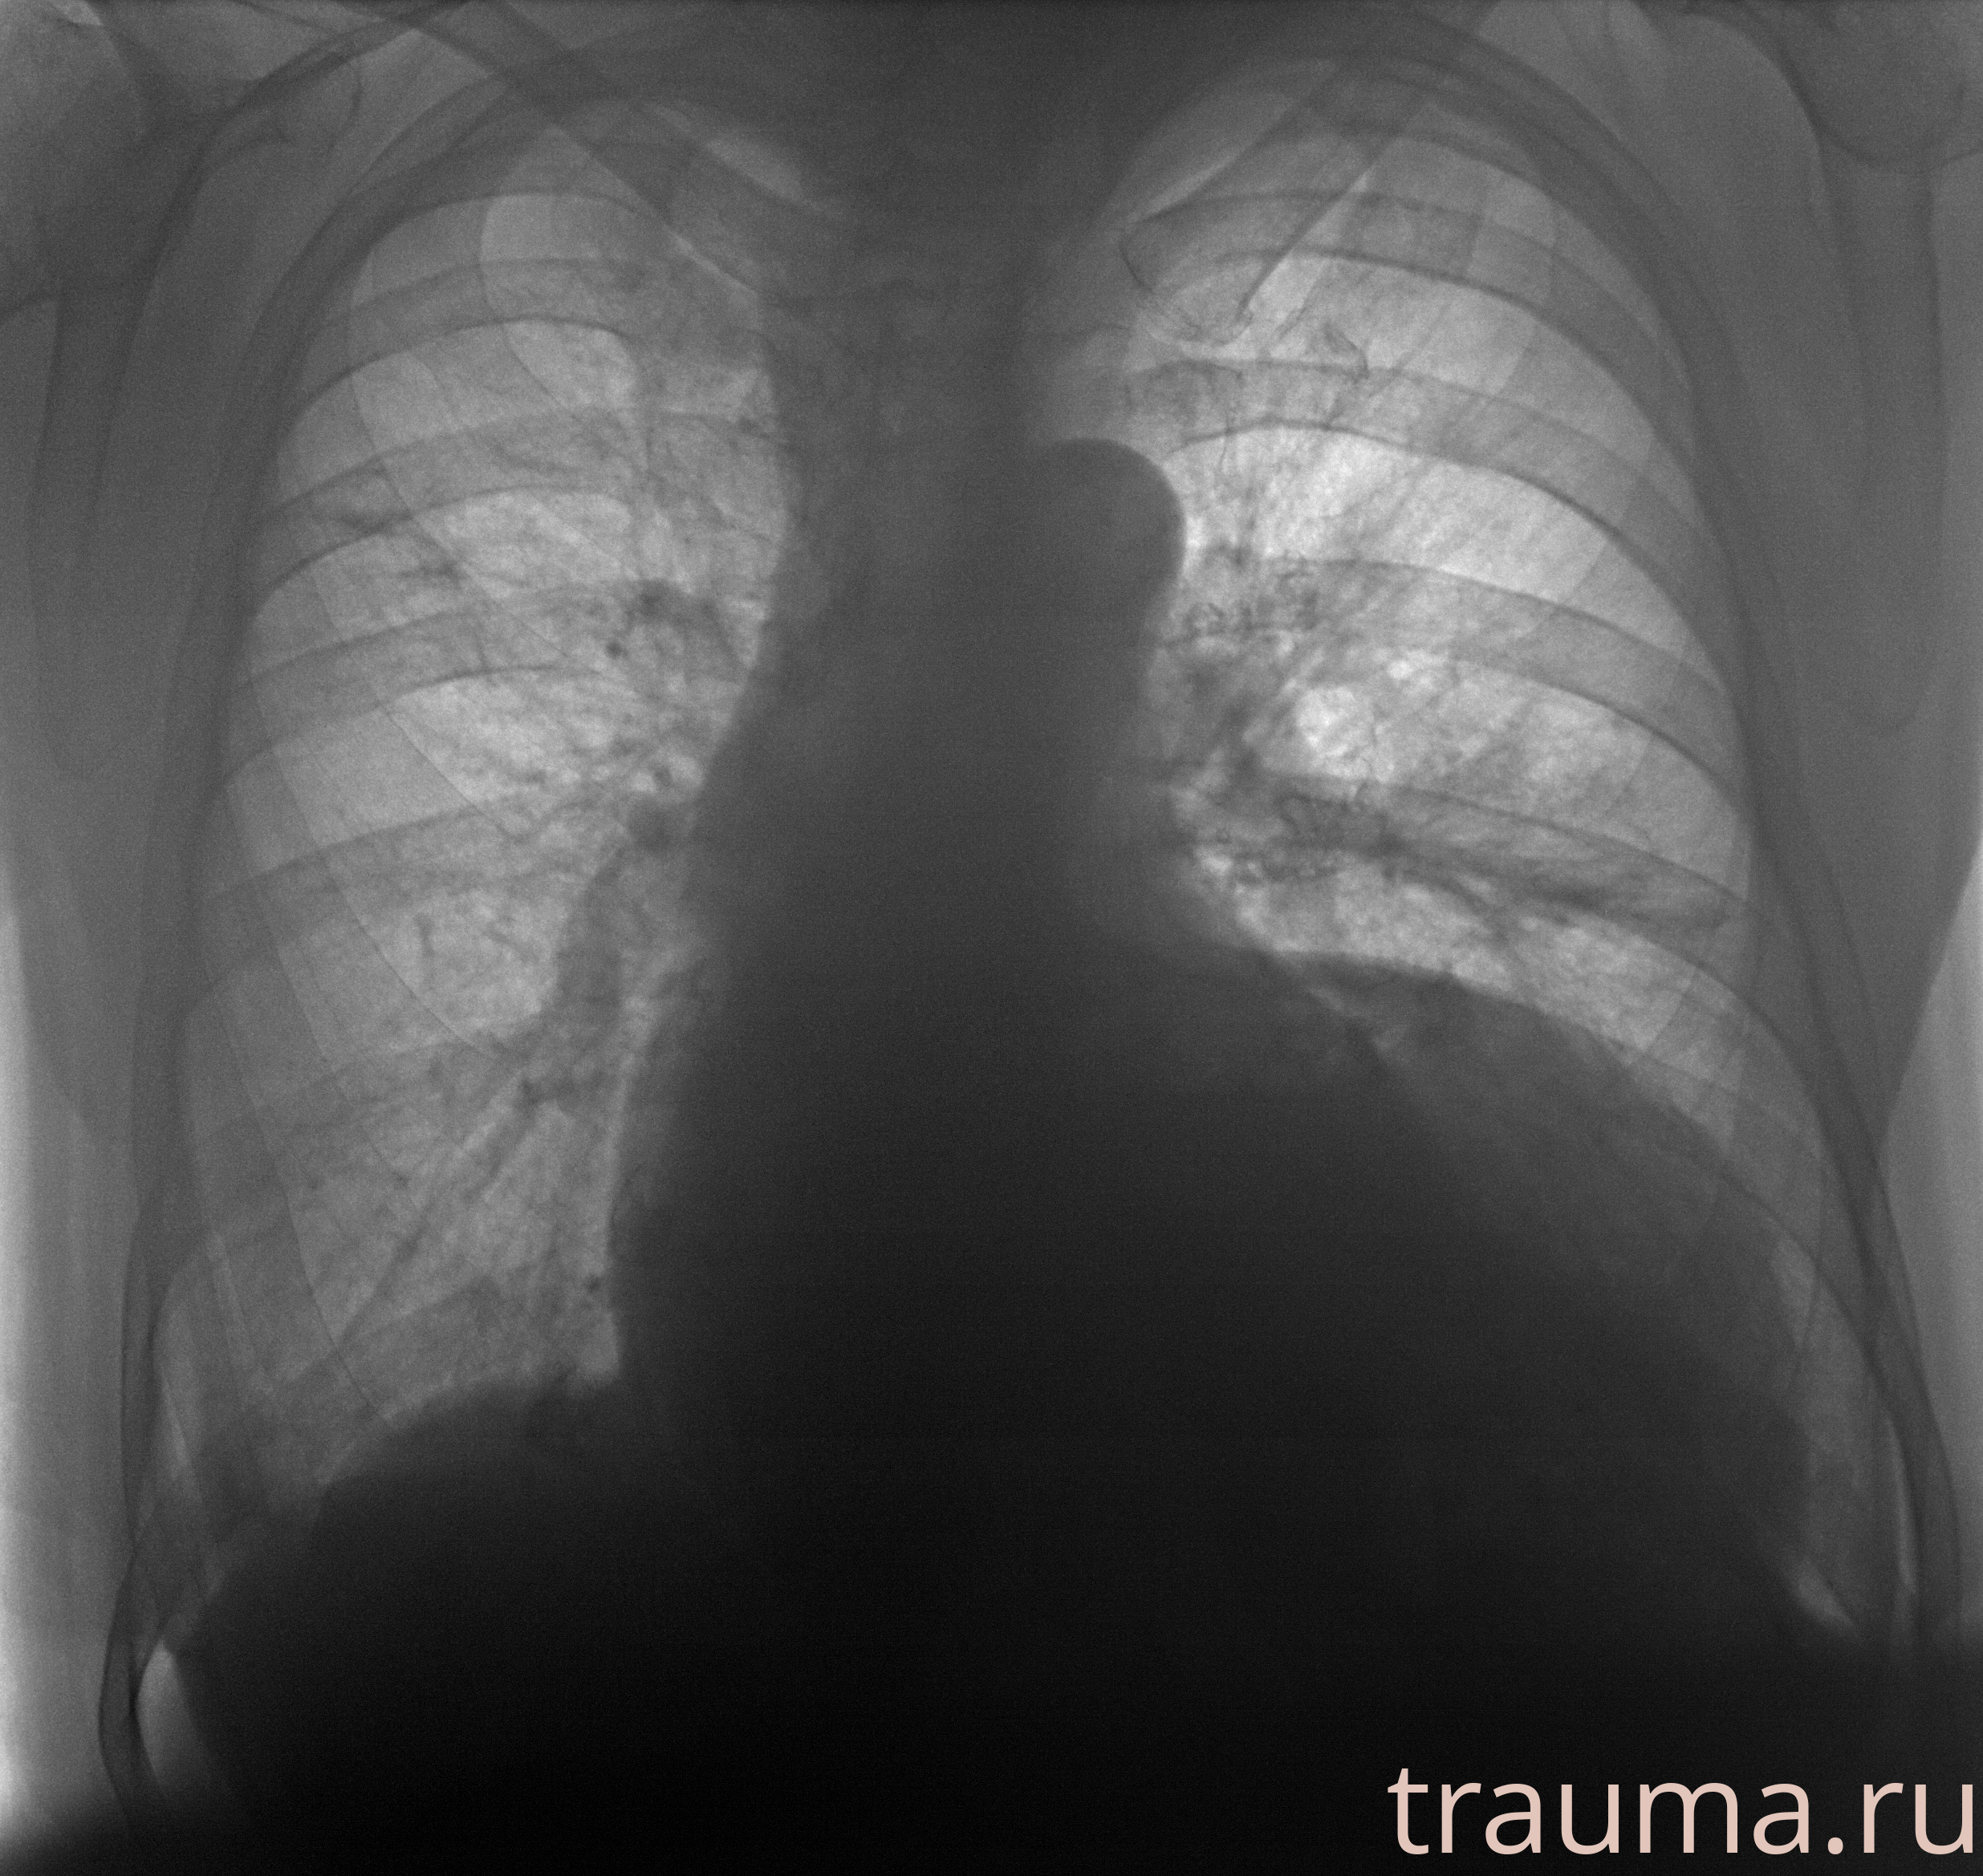

Рентгенограммы

Рентген на дому: по вашему адресу приезжает врач-рентгенолог, травматолог-ортопед с мобильным рентгеновским аппаратом, проводит диагностику травмы или заболевания, делает необходимые рентгенограммы, дает рекомендации по дальнейшему лечению. Получить качественные снимки в домашних условиях возможно благодаря уникальной методике, разработанной МосРентген Центром для института  Склифосовского

при переломе шейки бедра и пневмонии от компании МосРентген Центр - партнера Института имени Склифосовского